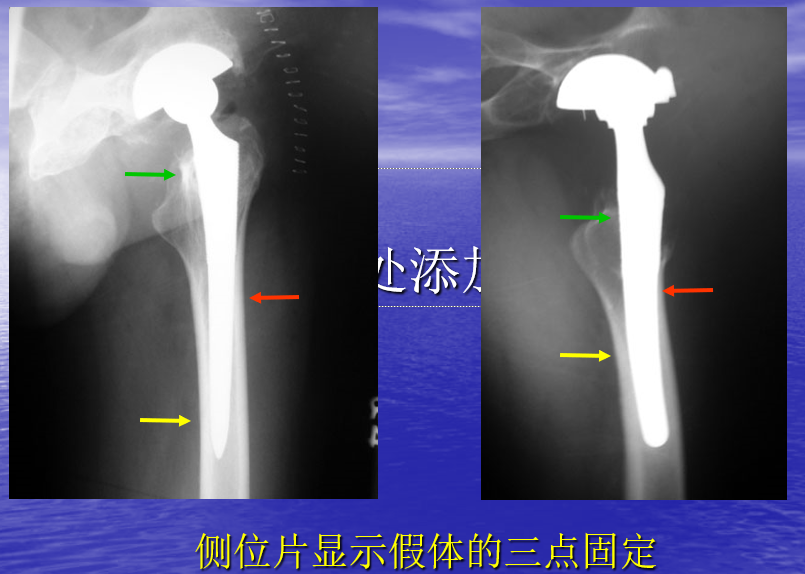

理想非骨水泥股柄的X线表现

• 骨长入固定

• 假体无沉降

• 多孔表面部分无反应线

• 多孔表面远端出现髓内骨增强现象

• 近端有应力遮挡引起的骨吸收

稳定的纤维长入-假体并无移位,或最初有轻微下沉,但一年后停止-多孔表面部分和光滑部分出现反应线,但不随时间变化-近端骨吸收轻微或没有出现-多孔表面部分和光滑部分的结合处没有出现髓内骨增强现象-轻微或没有基柱现象